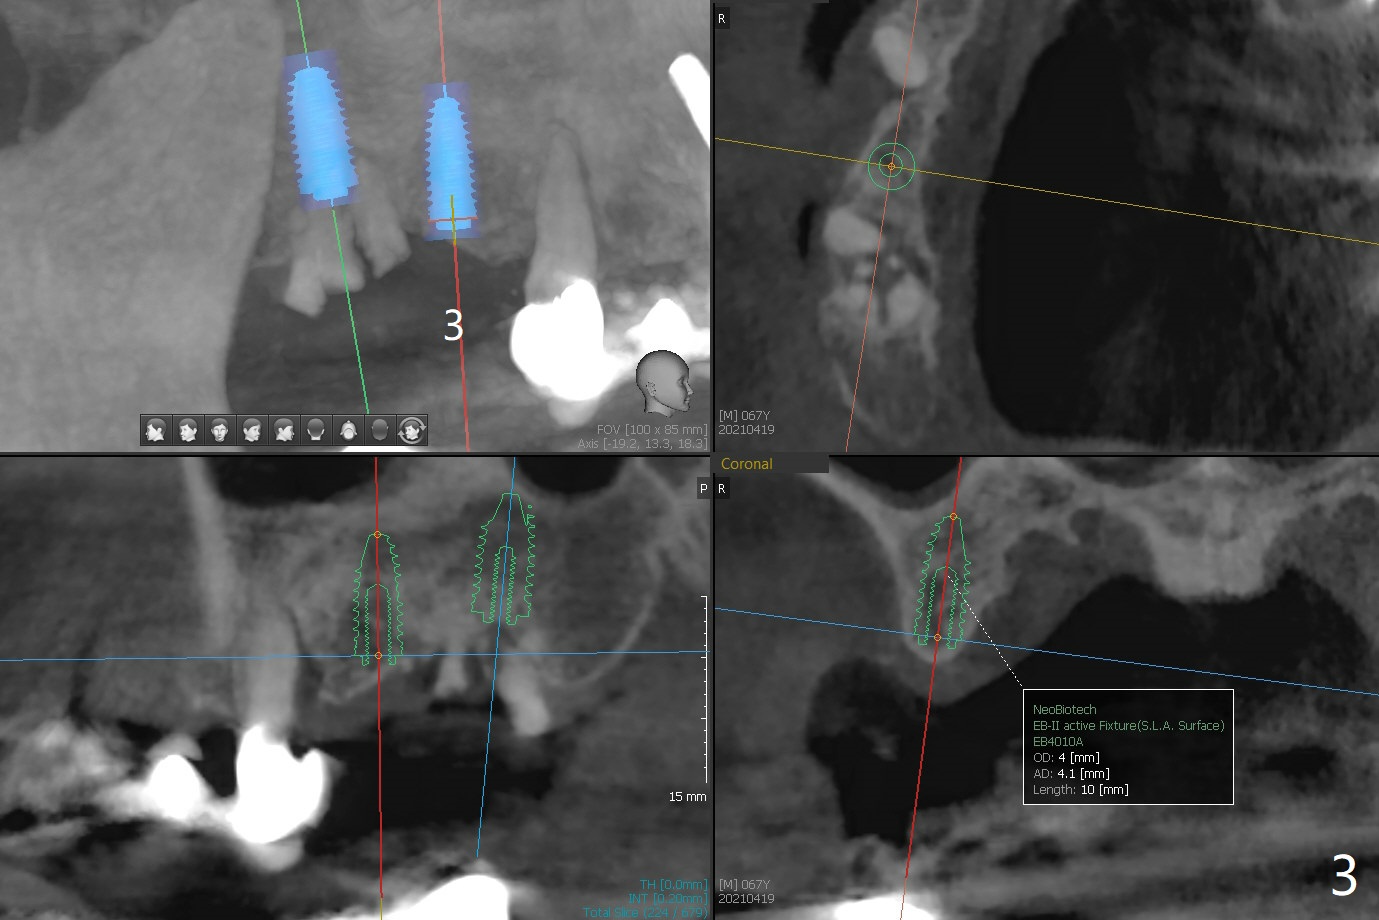

67岁男14号牙植牙牙冠粘固后两年回来处理右上(2-6)桥问题,撤除2,3单位(图一),准备种植(图二,三),3号牙牙槽嵴比较窄(图三),勉强植入4x10毫米植体,我想借助导板和它的钻头进行骨扩张,这样可以植入稍微大植体,例如4.5毫米。能不能最细钻头顺转,而再粗的钻头倒旋达到扩张目的?3号牙牙槽骨平均密度650单位。